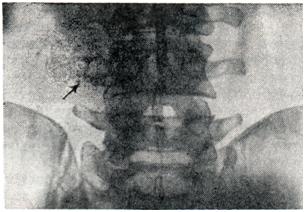

Значительно реже входными воротами актиномикоза является желудок, двенадцатиперстная кишка; еще реже — ободочная кишка (восходящая, поперечная, нисходящая, сигмовидная); очень редко — активно перистальтирующая тонкая кишка. У женщин, страдающих абдоминальным актиномикозом, часто выявляется специфическое поражение внутренних половых органов. Прогрессирование процесса при абдоминальном актиномикозе выражается в увеличении инфильтрата и необычайно обширном развитии спаек, объединяющих в общий конгломерат собственно актиномикозный инфильтрат и ближайшие органы и ткани, что может привести к развитию спаечной болезни. Слизистая оболочка кишечника остается интактной даже при значительных размерах очага актиномикоза и сдавлении просвета кишки. Реже абдоминальный актиномикоз протекает в форме абсцедирования с клиникой межкишечного абсцесса или с образованием склеротического процесса в кишечной стенке. Наиболее часто актиномикоз от места первичного аффекта распространяется в сторону передней брюшной стенки, формируя в ней абсцедирующий инфильтрат, вскрывающийся свищом на поверхности кожи. Второе по частоте направление распространения актиномикоза из слепой кишки — в забрюшинную клетчатку (рис. 4) — ретроабдоминальный актиномикоз. Ретроабдоминальный актиномикоз характеризуется необычной для этой инфекции диффузной инфильтрацией клетчатки, отсутствием четких границ очага, значительным отеком окружающих тканей, гнойным расплавлением по типу флегмоны и часто осложняется амилоидозом внутренних органов. Один из наиболее постоянных клинических симптомов при ретроабдоминальном актиномикозе — псоит. Из забрюшинной клетчатки актиномикоз может распространиться на позвоночник, грудную клетку, кости малого таза, нижних конечностей. Осложнением абдоминального актиномикоза может быть поражение печени, солитарное при контактном распространении, диссеминированное — при гематогенном. Параректальный актиномикоз (парапроктит актиномикозный) характеризуется появлением в клетчатке плотного неподвижного инфильтрата с относительно четкими границами. Возникшая инфильтрация распространяется по клетчатке, абсцедирует, образуя характерную бугристость, сдавливающую прямую кишку, иногда до полной обтурации. Вскрытие параректальных абсцессов при актиномикозе происходит, как правило, на кожу, крайне редко — в просвет кишки. Выявляется небольшая отечность слизистой оболочки прямой кишки, симптом пелотирования — выпячивание плотного инфильтрата в просвет кишки, реже — кровоточивость слизистой оболочки. Больные отмечают тенезмы, запоры. При фистулографии выявляется сеть анастомозпрующих свищевых ходов в параректальиой клетчатке. Первичный актиномикоз ягодичной области может развиться на месте ушиба, инъекции лекарственного вещества. Актиномикоз крестцовой области исходит, как правило, из эпителиальной копчиковой кисты. Из параректальиой или ягодичной клетчатки актиномикоз может распространиться на промежность, моче-половые органы. Актиномикоз моче-половых органов развивается в результате распространения процесса по контакту или гематогенно. Актиномикоз почек проявляется локальными болями, иногда в виде почечной колики, пальпируемым инфильтратом, гематурией. Если очаг актиномикоза локализуется в корковом веществе почки, то даже при большой его величине он может не иметь сообщения с полостью лоханки. Расположение очага в мозговом слое приводит к относительно раннему нарушению функции почки. При пиелографии в этих случаях наблюдается дефект наполнения почечных лоханок. При распространении процесса в околопочечную клетчатку развиваются явления паранефрита, ретроабдоминального актиномикоза. Из почки распространение актиномикоза возможно по нисходящим мочевыводящим путям, а также в другую почку. Поражение мочеточников характеризуется их деформацией, «изъеденностью», зазубренностью стенок, сужением просвета, что хорошо выявляется при контрастном рентгенологическом исследовании. Первичный актиномикоз мочевого пузыря встречается редко и связан обычно с инородными телами. Актиномикоз мочевого пузыря проявляется болезненным и учащенным мочеиспусканием, гематурией и протекает в дальнейшем по типу язвенногеморрагического или фибринозно-пленчатого цистита. На цистограмме может определяться дефект наполнения, при цистоскопии видна «опухоль» с редкими и относительно широкими полипозными образованиями. Актиномикоз наружных половых органов у мужчин и женщин развивается обычно как осложнение травмы, реже — в результате распространения процесса из тазовой клетчатки или мочевыводящих путей. Актиномикоз наружных половых органов у женщин обычно сопровождается гнойными выделениями из свищей, а у мужчин характеризуется развитием плотного, малоболезненного инфильтрата, что ведет, особенно при локализации у корня полового члена или на промежности, к дизурии. Абсцедирование актиномикоза сопровождается сильными болями и завершается образованием свища. Особенность актиномикоза полового члена — множественные свищи на коже и главным образом на головке, где «язвы» образуются не в результате некроза и отторжения тканей, а вследствие слияния близко расположенных устьев свищей. Эти свищи периодически закрываются, в отличие от мочевых, которые функционируют постоянно из-за стойкой рубцовой деформации мочеиспускательного канала. Часть мочи проникает и пропитывает клетчатку промежности, мошонки, таза, кавернозные тела полового члена, что значительно ухудшает состояние больных и облегчает присоединение вторичной инфекции. Описан случай актиномикоза полового члена, закончившийся гангреной последнего. Актиномикоз мошонки характеризуется множественными свищами, лимфостазом вплоть до слоновости ее. Кожа мошонки утолщается и уплотняется, бороздчатость ее становится грубой. Пальпировать яички и придатки удается с трудом. Снижения половой функции, как правило, не отмечается. Описаны единичные случаи актиномикоза предстательной железы, яичек и придатков, периуретральных желез. Актиномикоз внутренних половых органову женщин характеризуется значительных размеров очагом поражения, выходящим за пределы малоготаза; образуются сращения с кишечником и сальником. Влагалище сужается настолько, что влагалищное исследование становится невозможным или резко затрудненным. Наиболее часто поражаются придатки, реже — матка. Свищи могут открываться на кожу передней брюшной стенки, бедра, в область наружных половых органов и промежности, поясничную и ягодичную области, во влагалище, прямую кишку, мочевой пузырь и тому подобное. У некоторых больных в начале заболевания из половых путей появляются выделения белого цвета или гноевидные, количество выделений иногда достигает 1 л в сутки. Иногда отмечаются нарушение менструального цикла, ациклические кровотечения. Изменения в костях при актиномикозе имеют разнообразный характер и зависят от путей проникновения инфекции, преобладания одного из одновременно протекающих процессов (деструктивного, остеомиелогического и продуктивного, склеротического). При контактном пути распространения актиномикоза в первую очередь поражается надкостница, затем корковое вещество кости и, наконец, губчатое. Надкостница утолщается, уплотняется. В дальнейшем может обыз-вествляться (оссифицирующий периостит). Обызвествление межпозвоночных связок обусловливает деформацию позвоночника в форме бамбуковой палки. При гематогенном пути очаг актиномикоза напоминает центральный костный абсцесс, отличаясь от последнего зоной склероза вокруг, которая может быть едва заметна или резко выражена. Выраженность и увеличение зоны склероза вокруг очага актиномикоза в кости — благоприятный прогностический признак. Размеры очагов деструкции варьируют: солитарный очаг имеет обычно относительно большие размеры, множественные — меньшие. Актиномикоз не поражает хрящевую ткань и, как правило, суставы. Повидимому, именно поэтому актиномикоз позвоночника даже при обширном поражении не осложняется его искривлением. Своеобразная клинико-рентгенологическая картина наблюдается при поражении стопы (смотри Мадурская стопа). Актиномикоз головного мозга, развившийся в результате распространения инфекции контактно или по лимфатическим, путям из очага на лице и шее, в ретрофарингеальной клетчатке, протекает по типу гнойного, чаще базилярного менингита, менингоэнцефалита, солитарного абсцесса, который может достигать значительных размеров в той или иной части головного мозга, что и определяет клинику заболевания. Гематогенный актиномикоз головного мозга характеризуется множественными рассеянными актиномикомами в мозговой ткани и в оболочках мозга, что клинически проявляется как энцефалит, пахилептоменингит. Возможно сочетание контактного и гематогенного путей проникновения инфекции в головной мозг. Актиномикоз спинного мозга может развиться в результате контактного проникновения инфекции из средостения через межпозвоночные отверстия, эпидуральное пространство и клинически проявляется как радикуломенингит, острый гнойный менингит. Метастатические очаги в спинном мозге встречаются чрезвычайно редко, Спинной мозг при актиномикозе страдает чаще от сдавления, чем от непосредственного поражения. Имеются описания распространения актиномикоза по оболочкам сначала головного, затем спинного мозга с клиникой цереброспинального менингита. Очаг актиномикоза центральной нервной системы может в течение многих лет существовать латентно. Актиномикоз кожи может быть первичным и вторичным. Первичый актиномикоз кожи развивается в результате проникновения актиномнпетов извне при травмах, ранениях. Вторичный актиномикоз кожи наблюдается чаще, он развивается вследствие распространения инфекции из первичного очага во внутренних органах. Различают следующие клинические формы актиномикоза кожи. Узловатая форма. При первичном актиномикозе кожи — плотный или плотноэластический малоподвижный безболезненный инфильтрат в глубоких слоях кожи размером 3×4 см и более. Увеличиваясь, инфильтрат выступает над уровнем окружающей кожи, которая приобретает темно-красный цвет с фиолетовым оттенком (Цветной рис. 1 и 2). Рядом с основным очагом нередко развиваются новые, дочерние, эволюция их такая же. При вторичном актиномикозе кожи узлы крупнее, залегают глубже, спаиваясь с окружающими тканями. Узлы абсцедируют и вскрываются с образованием нескольких свищей — гуммозная форма актиномикоза кожи.